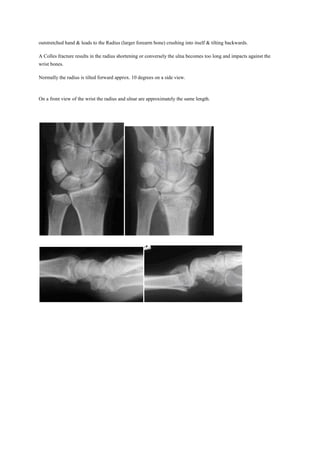

A Colles fracture results in the radius shortening or conversely the ulna becomes too long and impacts against the

wrist bones.

Normally the radius is tilted forward approx. 10 degrees on a side view.

On a front view of the wrist the radius and ulnar are approximately the same length.

Normal alignment Colles fracture with change in wrist alignment

A Colles fracture alters the alignment of the small bones (within the wrist. This can result in arthritis throughout the

wrist.